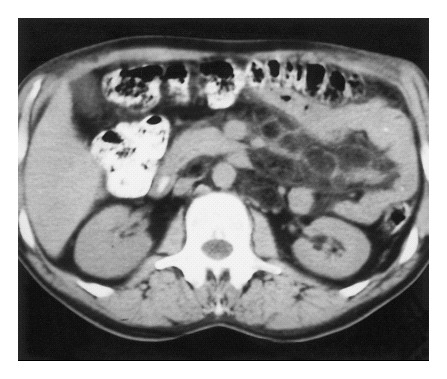

A chest x-ray (Panel A), CT scan of the chest (Panel B) and abdomen (Panel C),

and the results of a barium-enema examination of the small bowel (Panel D) are shown

below.

Panels C & D